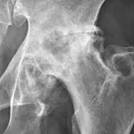

Fig. 9.10 Osteoarthritis. (Sources of images

Note: (1) the progressive roughening of the round ball and its socket,

(2) the decreasing clear space (cartilage and fluid) between them,

(3) and the extra rough bone (white material) around the joint.

Description English: Projectional radiography of the left hip of

a 65 year old man with pain upon hip movement. It

shows severe (Tönnis grade 3) osteoarthritis.